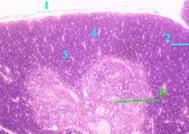

| Дольки и их части | а) Тимус покрыт капсулой (1) и отходящими от неё перегородками (2) разбит на дольки (3). б) В каждой дольке различают - на периферии – корковое вещество (4), плотно заселённое лимфоцитами и потому на препарате более тёмное, - и в центре – мозговое вещество (5), более светлое. |

Рис. 20.3

Тимус ребёнка

Окраска гем. и эозином

| Строма | Одна из особенностей тимуса – в том, что его строма имеет эпителиальную природу: | |

| представлена не ретикулярными клетками и одноимёнными волокнами, а эпителиоретикулярными клетками (без волокон). |

| Лимфоидные клетки | а) В подкапсулярной области – Т-лимфобласты (клетки класса IV). б) Глубже – созревающие Т-клетки, проходящие реаранжировку генов и два тура селекции. | а) В мозговом веществе – рециркулирующие Т-лимфоциты, попадающие в кровь и обратно через т.н. венулы с высоким эндотелием. б) Клетки стромы могут образовывать слоистые тельца Гассаля – округлые наслоения ороговевших эпителиоцитов. |

| Клетки стромы | Функциональные виды стромы: 1) опорные клетки, в т.ч. те, что отростками формируют гематотимусныйбарьер, 2) клетки-«няньки»; в их инвагинациях развиваются Т-лимфоциты; 3) секреторные клетки. | |

| Макрофаги | Обычные макрофаги, дендритные и интердигитирующие клетки. |